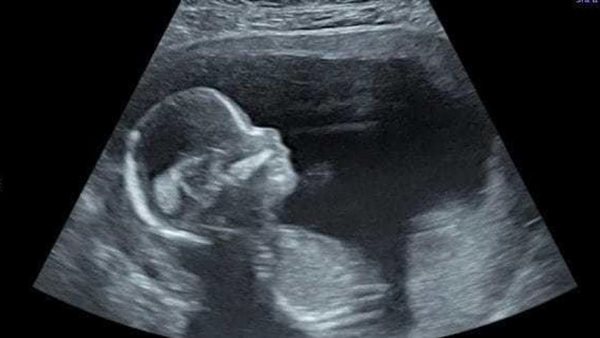

وحضرت سيدة في آخر الشهر الثامن من الحمل وبعد الكشف في عيادة متابعة الحمل الخطر بمستشفى دار صحة المرأة ببورسعيد، وبعد عمل إيكو قلب للجنين والفحوصات اللازمة داخل الرحم بواسطة الدكتورة نشوى حجازي أخصائية أمراض النساء والتوليد وطب الجنين، تبين وجود ارتشاح شديد وسوائل شديدة في الغشاء حول القلب، مما يؤثر على وظيفة القلب وحجم الرئة، ويشكل خطورة شديدة على حياة المولود مع أول نفس بعد لحظة الولادة، وذلك نتيجة ضغط الارتشاح على القلب وخاصة ان الأم لها تاريخ مرضي لطفل ذو عيب خلقي بالقلب.

وتم إجراء بزل ارتشاح شديد في الغشاء التامور للقلب، وإزالة السوائل الضاغطة على القلب في الثانية الأولى للولادة، داخل غرفة الولادة من خلال القسطرة، بواسطة فريق قسطرة قلب الأطفال بمستشفى النصر التخصصي، تم عمل إيكو للطفل بعد الولادة لتقييم حالة الطفل، وهو الآن في حالة مستقرة هو والأم.